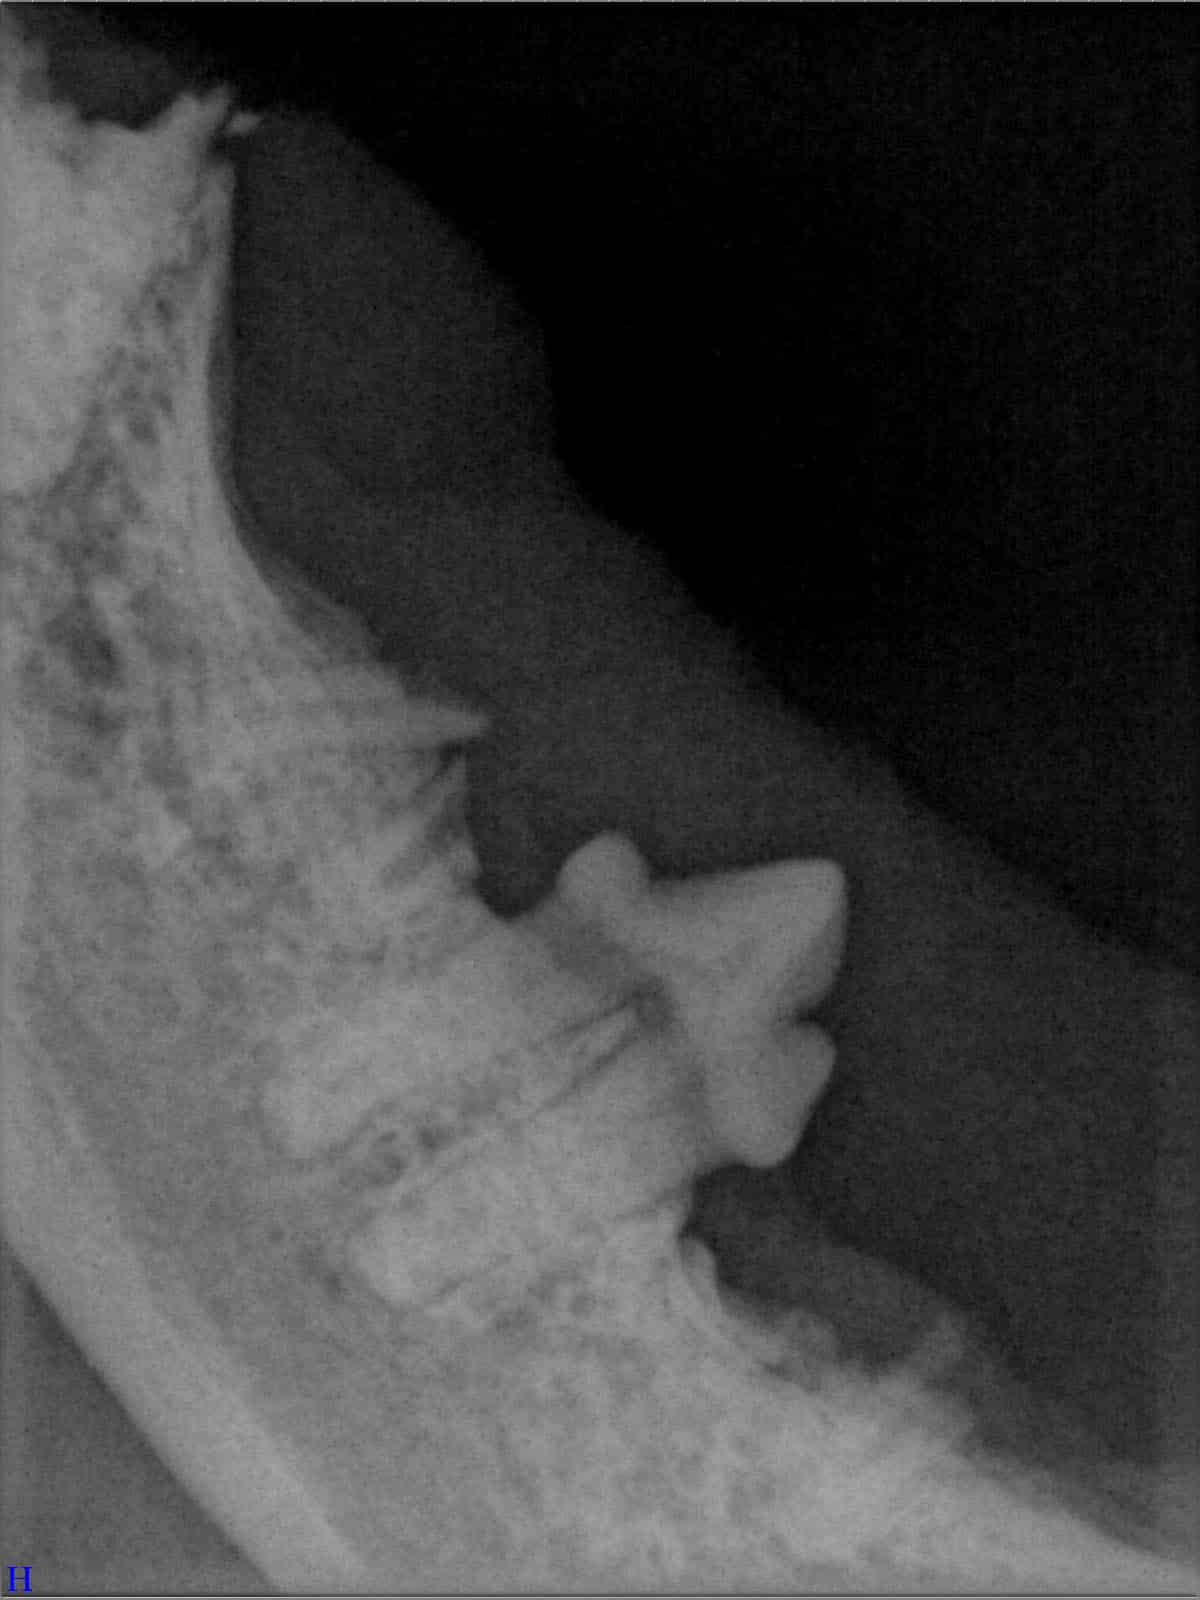

Röntgenbilder

(Fraktur + Wurzelentzündung durch Zahnstein)